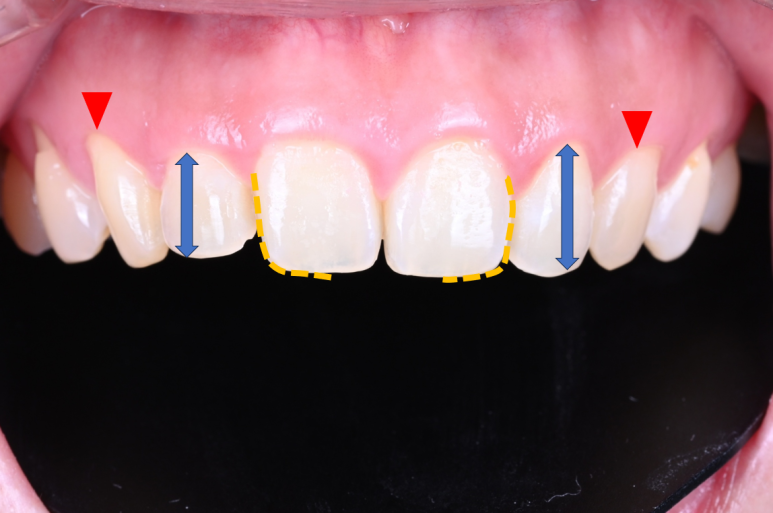

일단 가운데 두 치아 - 대문니가 모양이 다릅니다.

노란색 점선으로 된 부분을 보시면 차이를 바로 느끼실 수 있어요.

요기서 오는 비대칭 느낌을 바로 잡아야 했고,

파란색 화살표를 보시면, 대문니 옆에 있는 작은 앞니의 크기가 달라보입니다.

역시나 비대칭 느낌을 주는 포인트...

빨간색 화살표를 보시면, 잇몸의 길이가 다르죠?

이러한 작은 요소요소가 모여서 비대칭이 더욱 돋보이게 만드는 상태셨어요.

약간 아랫입술에 힘을 줘서 웃으신 상태긴 합니다.

치아의 색상도 좀 더 밝아지길 희망하셨습니다.

다만, 자연스러운 색상을 원하셨어요.